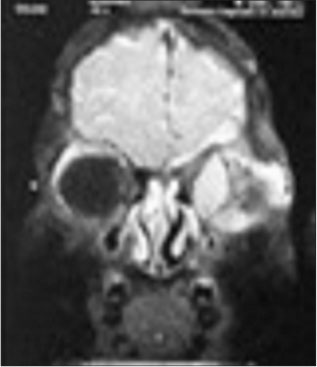

|?Figure. 4? A 6-year-old child with unilateral proptosis, diagnosed with precursor B- lymphoblastic lymphoma on biopsy (LTMMC, Mumbai, India)

|?Figure. 5? A Magnetic resonance imaging of brain and orbit showed large lobulated intraorbital mass occupying the retrobulbar portion, orbital apex, and extends into cavernous sinus, c/o precursor B- lymphoblastic lymphoma

Resection of the mass was done. Intraoperatively tumor was well circumscribed, not involving the optic nerve. Histopathological examination showed bits of tumor tissue showing diffuse dense monomorphous proliferation of lymphoid cells, infiltrating in the orbital soft tissue and muscle, and tumor cells were medium-sized lymphoid cells with thin nuclear membrane, delicate chromatin, indistinct nucleoli, brisk mitoses, and scant cytoplasm. On immunohistochemistry, tumor cells were negative for desmin, mic2, MPO, and synaptophysin and positive for LCA, CD20 and Tdt [Figure 6].